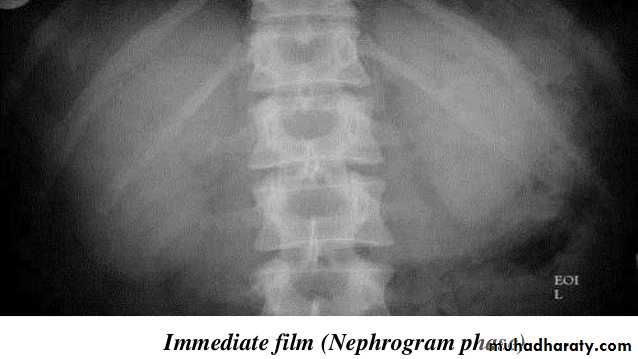

1.Nephrogram phase (Immediately after injection of contrast) .